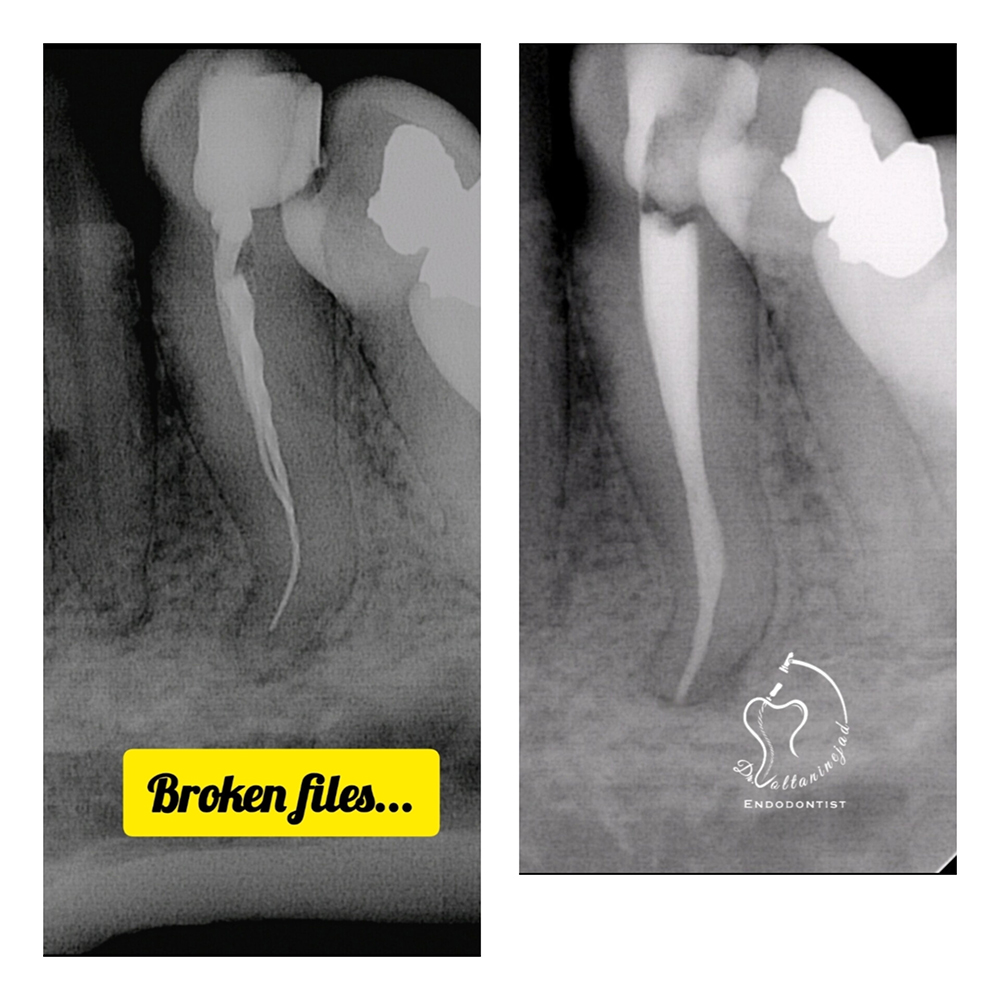

فایل شکسته در کانال ریشه

شکست ابزار در کانال می‌تواند مانع پاک‌سازی کامل شود. مدیریت این شرایط نیازمند تجهیزات پیشرفته و تجربه بالا است.